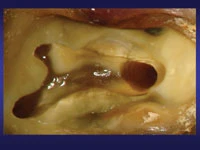

4: Khi làm sạch, sàn tủy khá giống một tầm bản đồ vời các đường màu đen có hình dạng chữ Y hay hình vuông. Lỗ vào ống tủy thường nằm ở cuối các đường này, như hình dưới